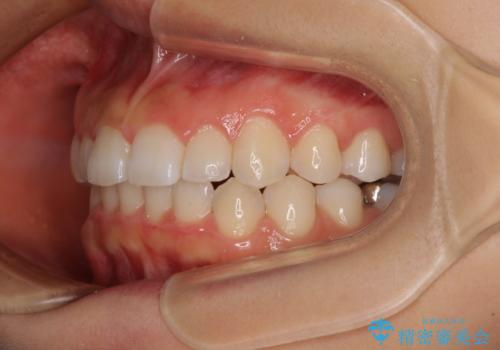

前歯のデコボコと突出感 インビザラインによる矯正治療

- 上下前歯のデコボコと、上顎前歯の突出感を気にして来院された患者様です。

インビザラインによる上下歯列の側方拡大と後方移動、IPR(歯と歯の間を削る)にるスペースの獲得により歯列を整えることとしました。

毎日22時間以上しっかりとマウスピースを装着していただいたので、スムーズに治療が進みました。歯と歯の間を削ることでうまくスペースコントロールでき、1年強で終えることができました。